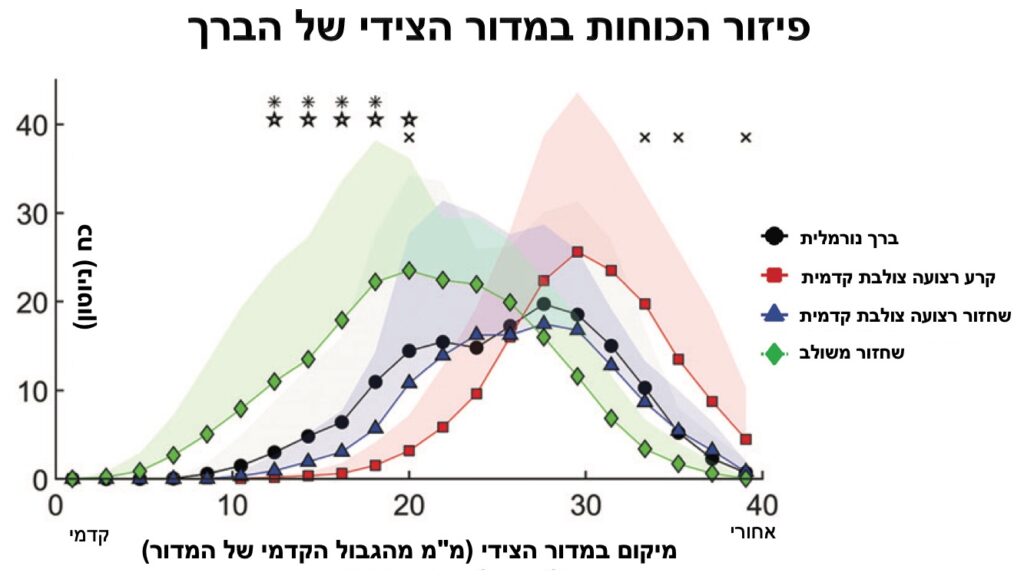

- הניתוח המשולב משנה את אופן פיזור הכוחות במדור הצידי בברך ביחס לברך נורמלית (כוחות גבוהים יותר בחלקים הקדמיים יותר של המדור).

- עם זאת, ברוב שילובי הכוחות שנבדקו, הניתוח המשולב אינו מעלה את הלחץ (contact stress) המקסימלי במדור.

- ניתן לראות באופן ברור את עליית הלחץ במדור הצידי לאחר קרע של הרצועה הצולבת הקדמית, מה שמסביר את השינויים השחיקתיים בברכיים לא יציבות בהעדר רצועה צולבת קדמית.

- בנוסף, ניתן לראות שניתוח מבודד לשחזור רצועה צולבת קדמית מוריד את הלחצים במדור הצידי חזרה ללחצים נורמלים.

הממצאים החדשניים מאפשרים לנו להבין טוב יותר את ההשפעות של הניתוח המשולב,

להתאים בצורה טובה יותר את הפרוצדורה הזו למטופלים ספציפיים ולבצע אותה טוב יותר.